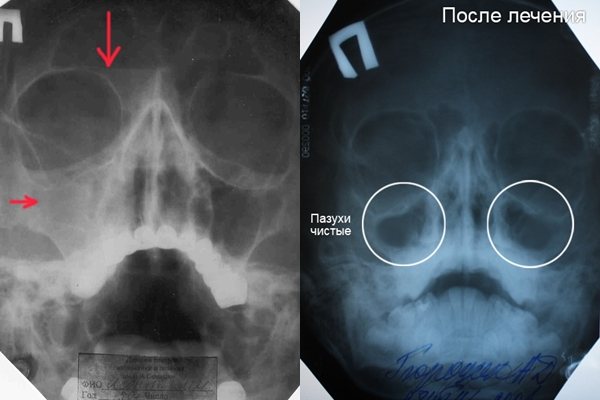

Вид гайморита на рентгеновском снимке

Рентгенограмма позволяет врачу точно оценить состояние гайморовых пазух и диагностировать присутствие нарушения.

Во время исследования на снимке изображаются лицевые кости светлого цвета, а затемнения появляются в тех местах, где расположены мягкие ткани. На результате диагностики четко просматриваются носовые пазухи, они находятся справа и слева от носа, прямо под глазницами. В норме глазницы и гайморовы пазухи имеют на рентгенограмме одинаковый цвет. Поэтому любое отклонение цвета пазух носа от цвета глазниц позволяет врачу заподозрить появление воспаления или патологии.

Если на фоне затемненных гайморовых пазух просматриваются белесые пятна, это указывает на скопление в пазухах жидкости. На рентгенограмме медики могут увидеть, насколько пазухи заполнены жидкостью.

Иногда на снимке просматривается тотальное затемнение на месте носовых пазух, подобное состояние указывает на большое количество скопившейся жидкости. Если заметно потемнение только у стенок, то у больного имеется набухание слизистой оболочки.

У здорового человека на снимке гайморовы пазухи имеют четкие очертания, а неровные края и утолщенные стенки свидетельствуют о присутствии воспалительного процесса.

Как выглядит гайморит

На фото показан двусторонний гайморит